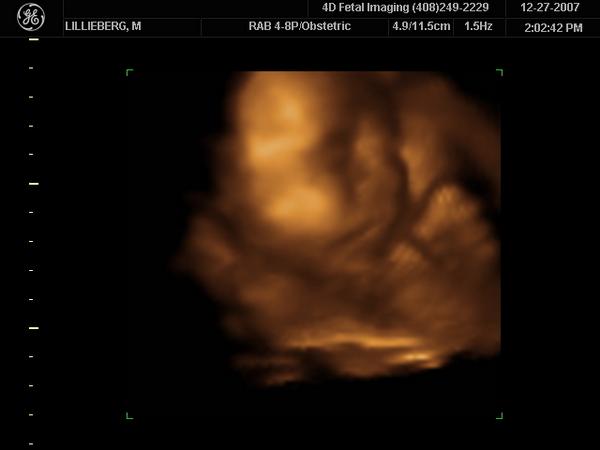

Enjoying Every Moment With My Daughter..

I've already met her.My little Ava.